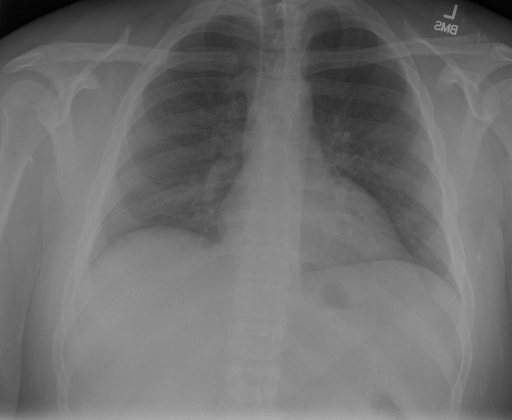

- (1)准备[诊疗报告(中文)](./data/Xray/openi-zh.json)和[X光影像](https://pan.baidu.com/s/13GBsDMKf6xBZBSHpoWH_EA?pwd=k9sh)在`data/Xray`文件夹下; - (2)开始训练: ```bash # 设置CUDA变量,主要是为了解决有时候直接训练而出现无法正确加载到显卡问题 export CUDA_VISIBLE_DEVICES=0,1,2,3 # 开始训练 bash finetune_XrayGLM.sh ``` 这里的复现过程非常简单,主要是很多过程我们都为大家准备好了,大家可以随时复现一个自己的`XrayGLM`。 ### 4.模型训练(通用) ## 效果展示 影像诊断: |X光影像|诊疗报告(医生)|XrayGLM| |:-|:-|:-| |![](./data/Xray/2_1.png)|根据X射线图像,心脏大小正常,肺部看起来很清晰。已经排除了肺炎、积液、水肿、气胸、腺病、结节或肿块的存在。该发现表明一切正常。换句话说,总体印象是胸部正常。|X光片显示,心脏大小正常。肺部没有气胸或胸腔积液的证据。骨骼结构看起来没有任何异常。总的来说,X光片表明没有发现急性心肺疾病的迹象。| |![](./data/Xray/2882_1.png)|X光图片显示没有扭曲的区域、可疑的骨质不透明度或胸腺积液。心脏大小轻微增大,但非常稳定。此外,没有气胸的证据,肺野也正常。总体来说,X光片显示没有急性心脏异常,但要注意轻微的心脏扩大。|X光片显示,心脏大小正常。肺部和纵隔轮廓清晰,没有气胸或胸腔积液的证据。骨骼结构完整,没有任何急性异常。| |![](./data/Xray/2577_1.png)|心影形态在正常范围内。没有急性骨质异常。有可能出现没有明显的吸水或肺实质状况的线索。没有大面积积液或气胸。有可能怀疑其有误吸或肺实质问题。为了确诊和治疗,可能需要进行适当的影像学随访。|心脏大小正常,肺部和纵隔轮廓清晰。没有急性异常或活动受限的证据。没有任何明显的气胸、胸腔积液或肺不张的迹象。此外,也没有发现任何局灶性骨质异常或其他急性疾病。| 多轮对话: |X光影像|诊疗报告(医生)| |:-|:-| |![](./data/Xray/861_1.png)|右侧主动脉突出观察到。心脏大小正常。胸部未发现明显的肺气肿、胸膜积液或可疑的肺部病变。报告指出已知右侧主动脉情况正常。| ```bash >> X光影像路径:./data/Xray/861_1.png >> 用户:这是一张什么图? >> XrayGLM:这张图片显示的是一张肺部检查的X光片。 >> 用户:请描述这张胸部X光片的诊断结果 >> XrayGLM:心脏大小正常,肺部清晰。没有急性心肺疾病的证据。 >> 用户:是否存在肺气肿? >> XrayGLM:没有肺气肿。心脏大小正常,肺部清晰。没有发现急性心肺疾病的证据。 >> 用户:平时饮食该注意什么? >> XrayGLM:饮食应该健康,均衡。建议增加蛋白质的摄入量,因为蛋白质有助于维持肌肉和骨骼的健康。多食用蔬菜、水果、全谷物以及健康的脂肪来源如橄榄油、鱼类等可以帮助获得足够的维生素和矿物质。此外,避免过度饮酒或吸烟,这些习惯可能会对心脏健康产生负面影响。 ``` ## 未来展望 1. 模型的能力更多来源于数据的支持,`OpenI-zh`作为微调数据集,其数据量足以支持研究,在更广泛的任务和性能表现上,我们认为**在大规模数据集上预训练并在高质量少量数据集上微调是一种可行的方案**; 2. 普遍意义的理解上,视觉多模态模型=视觉模型+语言模型。除了需要关注视觉模型信息与语言模型输出的搭配外,还需要**额外关注到语言模型的加强,在人机的对话中,尤其是医疗语言模型的问答上,除了专业的医疗问题回答,带有人文情怀的有温度的回答更应该是我们追寻的目标**。 ## 项目致谢 1. [VisualGLM-6B](https://github.com/THUDM/VisualGLM-6B)为我们提供了基础的代码参考和实现; 2. [MiniGPT-4](https://github.com/Vision-CAIR/MiniGPT-4)为我们这个项目提供了研发思路; 3. ChatGPT生成了高质量的中文版X光检查报告以支持XrayGLM训练; 4. [gpt_academic](https://github.com/binary-husky/gpt_academic)为文档翻译提供了多线程加速; 5. [MedCLIP](https://github.com/RyanWangZf/MedCLIP) 、[BLIP2](https://huggingface.co/docs/transformers/main/model_doc/blip-2) 、[XrayGPT](https://github.com/mbzuai-oryx/XrayGPT) 等工作也有重大的参考意义; ![](./assets/images/mpu.png) 这项工作由[澳门理工大学应用科学学院](https://www.mpu.edu.mo/esca/zh/index.php)硕士生[王荣胜](https://github.com/WangRongsheng) 、[段耀菲](https://github.com/IsBaSO4) 、[李俊蓉](https://github.com/lijunrong0815)完成,指导老师为檀韬副教授、[彭祥佑](http://www.patrickpang.net/)老师。 *特别鸣谢:[USTC-PhD Yongle Luo](https://github.com/kaixindelele) 提供了有3000美金的OpenAI账号,帮助我们完成大量的X光报告翻译工作 ## 免责声明 本项目相关资源仅供学术研究之用,严禁用于商业用途。使用涉及第三方代码的部分时,请严格遵循相应的开源协议。模型生成的内容受模型计算、随机性和量化精度损失等因素影响,本项目无法对其准确性作出保证。即使本项目模型输出符合医学事实,也不能被用作实际医学诊断的依据。对于模型输出的任何内容,本项目不承担任何法律责任,亦不对因使用相关资源和输出结果而可能产生的任何损失承担责任。 ## 项目引用 如果你使用了本项目的模型,数据或者代码,请声明引用: ```bash @misc{wang2023XrayGLM, title={XrayGLM: The first Chinese Medical Multimodal Model that Chest Radiographs Summarization}, author={Rongsheng Wang, Yaofei Duan, Junrong Li, Patrick Pang and Tao Tan}, year={2023}, publisher = {GitHub}, journal = {GitHub repository}, howpublished = {\url{https://github.com/WangRongsheng/XrayGLM}}, } ``` ## 使用许可 此存储库遵循[CC BY-NC-SA](https://creativecommons.org/licenses/by-nc-sa/4.0/) ,请参阅许可条款。